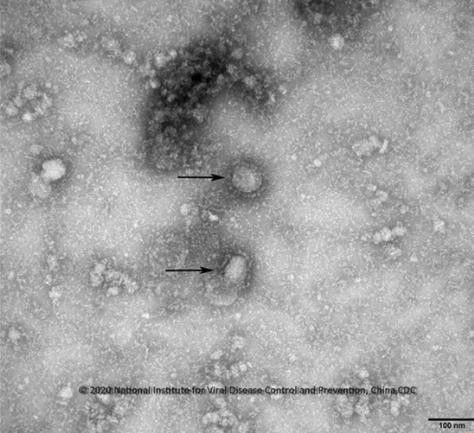

| ▲사진: 질병관리본부 |

중국 톈진(天津) 대학 연구진이 신종 코로나바이러스 감염증(코로나19) 경구 백신을 개발해 임상 시험을 추진 중인 것으로 전해져 주목된다.

25일 환구망(環球網) 등 중국 언론에 따르면 톈진대 생명과학대 황진하이(黃金海) 교수 연구팀은 최근 코로나19 바이러스의 S 단백질을 타깃으로 양조효모를 넣어 항체를 생성한 것으로 알려졌다.

이 백신의 작동 방식은 코로나19 바이러스의 S 단백질과 숙주 세포의 바이러스 수용체 결합을 막아 감염에 걸리지 않도록 하는 것으로 현재 연구팀은 이 경구 백신의 임상 시험을 위해 협력 파트너를 모색하는 중인 것으로 전해졌다.